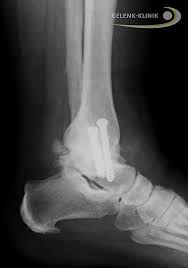

Einige Betroffene fühlen sich aber auch in einem kürzeren Zeitraum fit genug um ihre Arbeit wieder aufzunehmen. 6 Wochen das erste Mal wieder auf dem Rad und nach ca. Nach einer Operation sollten Sie den Fuß vier bis sechs Wochen nicht mit mehr als 15 bis 20 Kilogramm teilbelasten.

Im Anschluss an die OP muss der Knöchel mehrere Wochen ruhig lagern. Er wenn der Patient nicht mehr als arbeitsunfähig gilt darf er auch wieder ein Fahrzeug führen. Eine gewisse Menge an Heilung muss zu Beginn stattfinden aber mit der Zeit kann eines Ihrer Ziele sein nach dem Bruch wieder zu laufen.

Erst nach sechs Wochen dürfen Sie das Sprunggelenk wieder voll belasten. Genauere Angaben erhalten Sie. Wenn das Sprunggelenk gebrochen war dauert die Heilung meist bis zu drei Monate.

Meistens wird das Metall nach zirka 12 bis 18 Monaten wieder herausgenommen. Mein Arzt sagt jetzt ich soll nich ungefähr 2 Wochen nicht belasten ich kann meinen Fuß aber auch schon ohne Schmerz belasten und normal laufen.

Das als kleine Aufmunterung. Wenn Sie einen gebrochenen Knöchel erlitten haben und eine Operation mit Platten und Schrauben haben müssen um die Fraktur zu reduzieren werden Sie sich fragen wann Sie wieder zum Laufen kommen können. Erst nach sechs Wochen dürfen Sie das Sprunggelenk wieder voll belasten. 12 Wochen volle Belastung auf dem Bike wieder möglich. Du wirst erst wieder laufen lernen müssen. Ansonsten besteht die Gefahr von Folgeschäden wie der Entstehung einer Pseudarthrose Falschgelenkbildung Monate bis die alte Beweglichkeit wieder hergestellt und der Fuß komplett schmerzfrei ist. Ich hatte vor 2 Wochen am 25012019 meine Entfernung der Syndesmoseschrauben nach über 12 Wochen besser spät als nie nach einer trimalleolaren Sprunggelenksfraktur. Das als kleine Aufmunterung. Sportlich aktiv werden dürfen Sie erst wieder nach drei bis sechs Monaten.

Sportlich aktiv werden dürfen Sie erst wieder nach drei bis sechs Monaten. Sportlich aktiv werden dürfen Sie erst wieder nach drei bis sechs Monaten. Nach einer Operation sollten Sie den Fuß vier bis sechs Wochen nicht mit mehr als 15 bis 20 Kilogramm teilbelasten. Wenn das Sprunggelenk gebrochen war dauert die Heilung meist bis zu drei Monate. Quellen anzeigen Quellen ausblenden Gelenk-Doktor - Rehabilitation Sport Alltag und Erfahrungen mit der Sprunggelenksprothese. Das als kleine Aufmunterung. Er wenn der Patient nicht mehr als arbeitsunfähig gilt darf er auch wieder ein Fahrzeug führen.